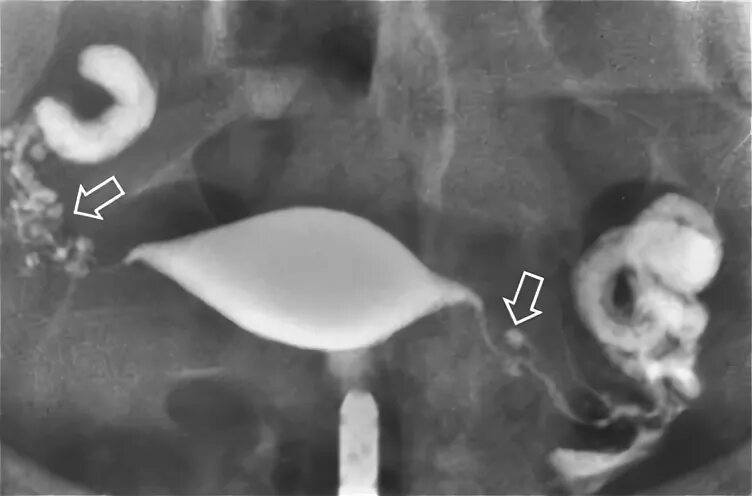

Сальпингит и оофорит что это